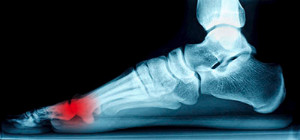

Caring for Heels Spurs

Heels spurs are often defined as a buildup of calcium deposits that form on the underside of the heel bone. When the foot muscles or ligaments are inflamed or strained, a heel spur may develop. Heel spurs can be particularly painful when partaking in activities such as walking, running, or jogging. To help care for a heel spur, it’s suggested that the affected foot is regularly rested and iced. Performing stretches before getting out of bed, wearing properly fitted shoes as well as inserts, and maintaining a healthy weight, can all benefit in relieving the discomfort of a heel spur. In order to treat this condition, it’s suggested you seek the professional care of a podiatrist.

Heels Spurs

Heel spurs are formed by calcium deposits on the back of the foot where the heel is. This can also be caused by small fragments of bone breaking off one section of the foot, attaching onto the back of the foot. Heel spurs can also be bone growth on the back of the foot and may grow in the direction of the arch of the foot.

Older individuals usually suffer from heel spurs and pain sometimes intensifies with age. One of the main condition's spurs are related to is plantar fasciitis.

Pain

The pain associated with spurs is often because of weight placed on the feet. When someone is walking, their entire weight is concentrated on the feet. Bone spurs then have the tendency to affect other bones and tissues around the foot. As the pain continues, the feet will become tender and sensitive over time.

Treatments

There are many ways to treat heel spurs. If one is suffering from heel spurs in conjunction with pain, there are several methods for healing. Medication, surgery, and herbal care are some options.